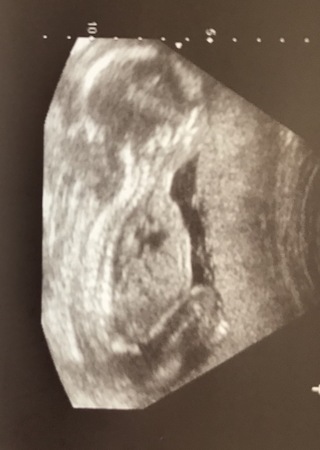

妊娠20週目エコー写真 胎児の大きさや胎動の様子 性別 妊娠中期 All About

医師監修 妊娠20週のエコー写真を多数掲載 みんなのエピソードつき マイナビウーマン子育て

妊娠20週のエコー写真です 横向きなのですが 性別ってわかりますか Yahoo 知恵袋